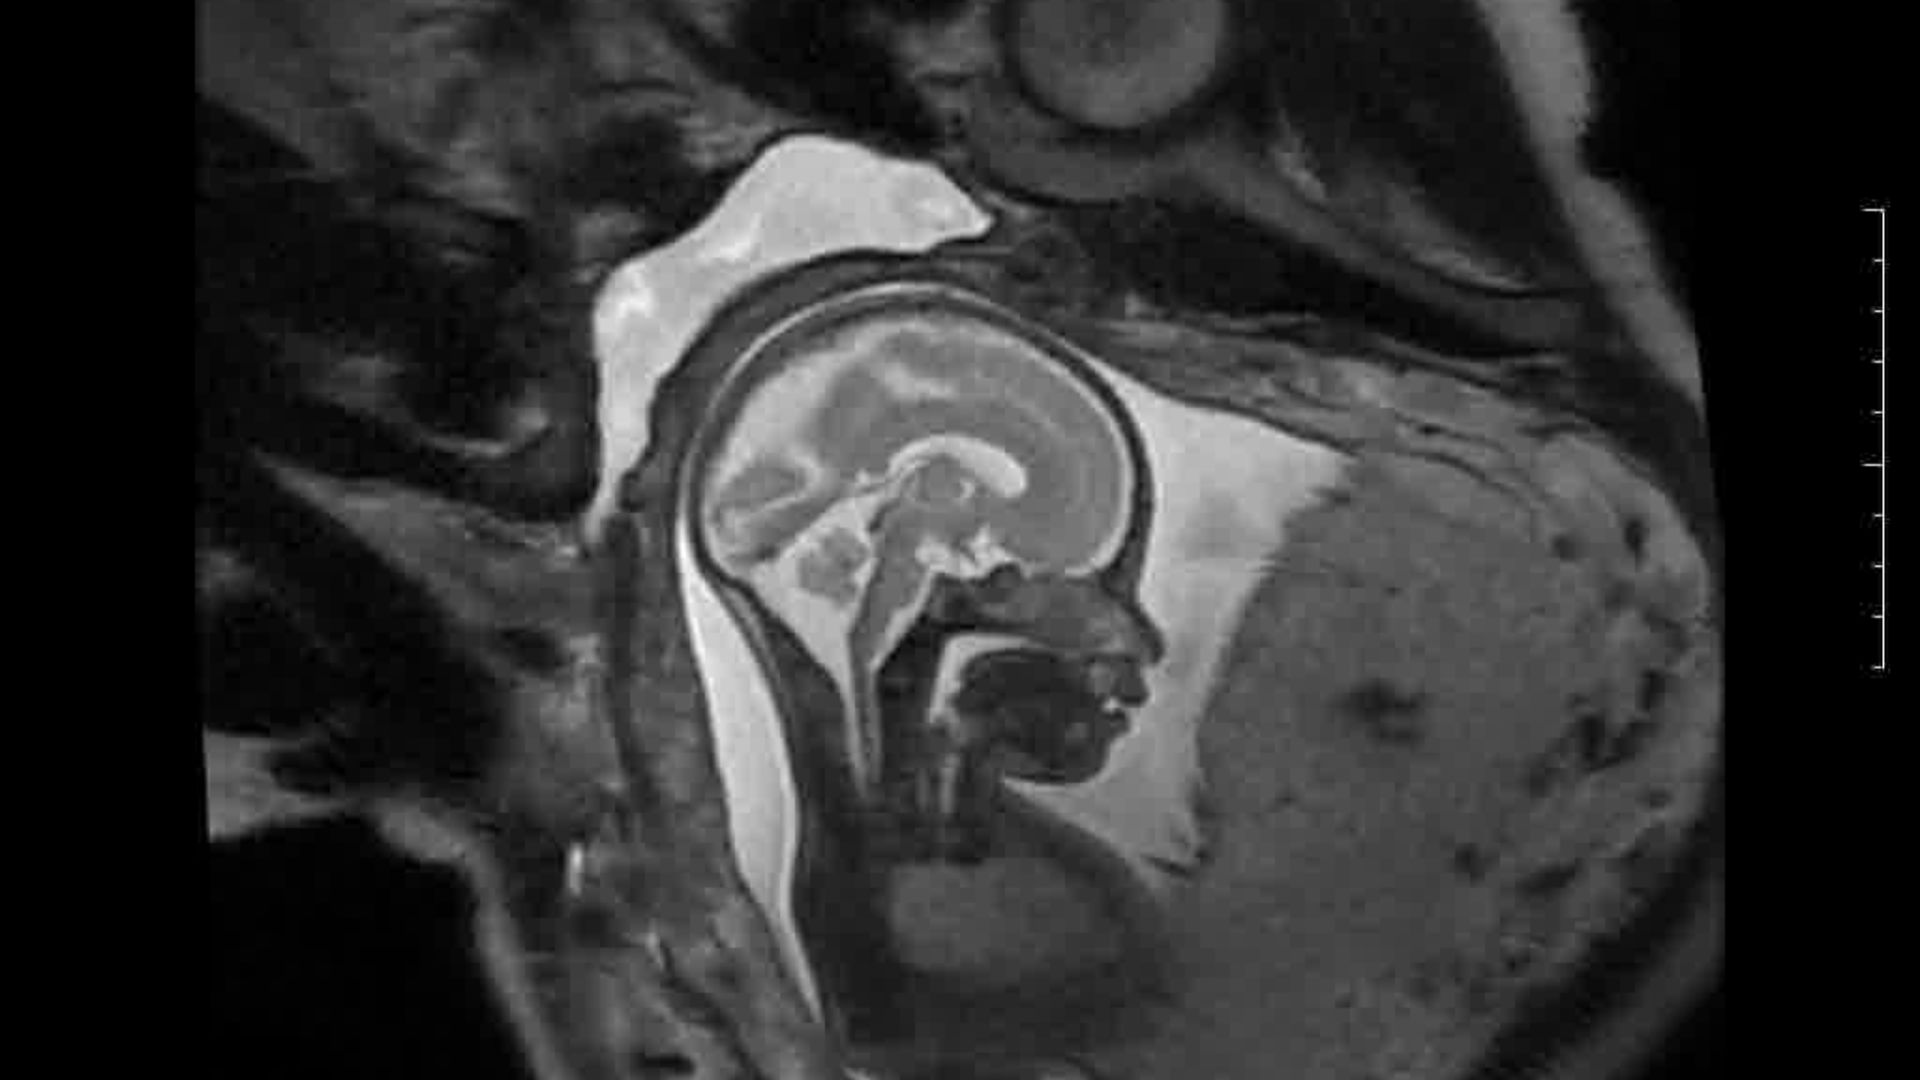

L’Université Paris Cité franchit une nouvelle étape dans le domaine de l’imagerie médicale anténatale avec l’acquisition d’un système d’Imagerie par Résonance Magnétique (IRM) 1,5T ARTIST™ de GE HealthCare. Cet équipement de pointe renforce les capacités de la Plateforme LUMIERE à l’hôpital Necker-Enfants malades, plateforme intégrée de soins, de recherche clinique et d’enseignement en imagerie médicale de la femme enceinte, du fœtus et du placenta.

Depuis 2020, la Plateforme LUMIERE offre aux femmes enceintes volontaires, entre 16 et 36 semaines d’aménorrhée et suivies à l’hôpital Necker-Enfants malades, la possibilité de participer activement à l’avancée de la recherche en médecine fœtale, tout en bénéficiant d’une IRM fœtale au cours de leur grossesse, réalisée dans un cadre sécurisé et encadré.

L’inclusion de ces patientes, depuis leur accueil jusqu’à la réalisation des examens d’imagerie, puis l’analyse des images et l’interprétation des résultats par des équipes expertes, enrichit une base de données structurée, unique au monde, au service de la recherche et de l’innovation en imagerie anténatale et en médecine fœtale.